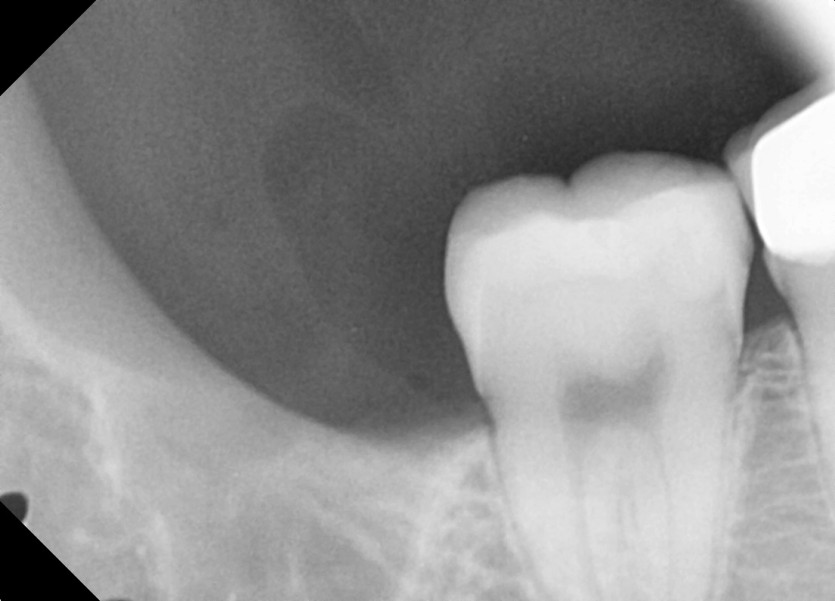

#18,48 사랑니 발치

구강 외과 전문의가 당일 발치했습니다.